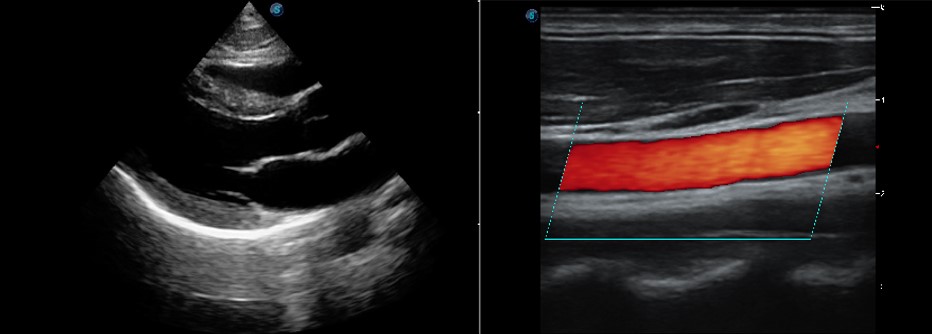

Chế độ Anatomic M

Anatomic M Mode giúp bạn quan sát chuyển động của cơ tim ở các giai đoạn khác nhau bằng cách đặt các đường mẫu một cách tự do. Nó đo chính xác độ dày cơ tim và kích thước tim của ngay cả những bệnh nhân khó khăn, đồng thời hỗ trợ chức năng cơ tim và đánh giá chuyển động thành LV.

Hình ảnh Doppler mô

P20 được ưu đãi với Hình ảnh Doppler Mô cung cấp vận tốc và các thông tin lâm sàng khác về chức năng cơ tim, tạo điều kiện cho các bác sĩ lâm sàng có khả năng phân tích và so sánh chuyển động của các bộ phận khác nhau của tim bệnh nhân.